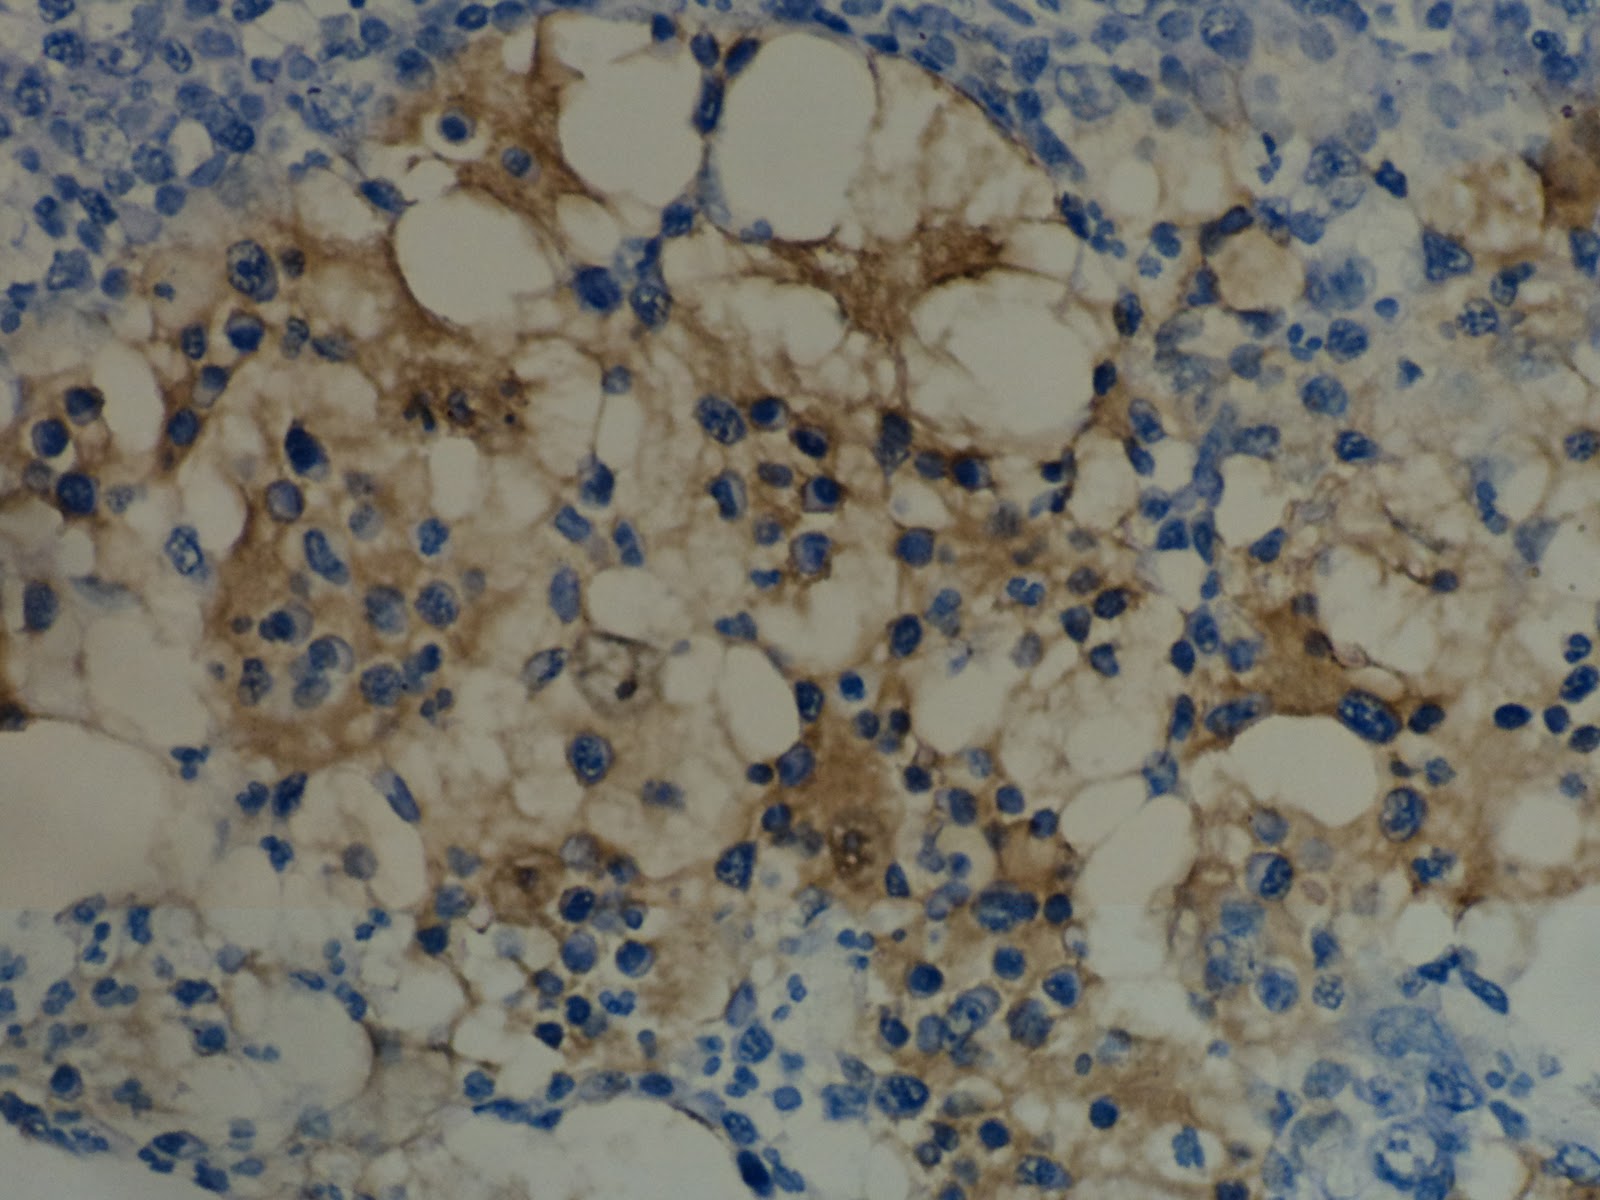

Rosai- Dorfman disease/ Sinus hitiocytosis with massive lymphadenopathy - histopathilogy s-100